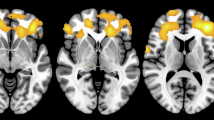

In PD, symptoms frequently start on one side and the disease remains relatively asymmetric at least during the first years45. If direct causality exists between caudate terminals integrity and RT severity, a lateralized finding is expected to emerge. In line with our general results, both right and left CBR were positively and significantly associated with total RT score (Fig. 5C). This was not seen for the putamen. However, we were struck by the finding that this was driven by positive ipsilateral correlations. Right and left RT scores were positively associated, respectively, with right (r = 0.24, P < 0.001) and left (r = 0.19, P < 0.001) CBR (Fig. 5C). This result was unexpected and not aligned with current knowledge on basal ganglia motor control circuits, where contralateral representation has been consistently described.

Having found that the presence of RT is related to higher CBR, we questioned if the ipsilateral correlations between RT and CBR could be spurious and emerge simply from the combination of 1) a globally higher CBR in patients with any type of RT and 2) a high correlation between contralateral and ipsilateral CBR (as found in the PPMI cohort, r = 0.779, P < 0.001).

To achieve this, we created an in silico model with 3 main assumptions (1) Patients with RT have a higher CBR than patients without, (2) Tremor amplitude (i.e, RT values above 0) on the reference side is not associated with CBR, (3) Ipsi and contralateral CBR are highly correlated (~0.80). With this model, we demonstrate these assumptions are enough for a positive ipsilateral correlation with tremor on the reference side to emerge (Fig. 5D) but do not explain the absence of a contralateral correlation.

PD is known to be an asymmetric disease. If we restrict our analysis to patients selected by having any parkinsonian symptom on the reference side (100% of subjects have at least a unilateral disease) we are sure that in a large population, these symptoms will be less common contralaterally (<100% of subjects have a bilateral disease). If the tremor is present on the reference side, it is more likely to have a more intense nigro-striatal degeneration contralaterally (therefore, a lower average contralateral, than ipsilateral PBR and CBR). These, and other intuitions were supported by the data in the PPMI cohort (Supplementary Fig. 7) and led us to add one last assumption to our model: 4) PD patients with RT on one side have a lower contralateral CBR, and PD patients without tremor on the reference side have a lower ipsilateral CBR. This assumption was evident when we analysed the PPMI dataset (Fig. 5E).

Using the left side as a reference and the mean and standard deviation of CBR in the PPMI dataset (Fig. 5E) we simulated CBR values (Fig. 5F) with all 4 assumptions. We found that the emerging correlations from our simulations were very similar to the ones originating from real data (real data: CBR contralateral, r = −0.061, ipsilateral, r = 0.190; simulated: CBR contralateral, r = −0.051, ipsilateral, r = 0.179). Details on further validation of this model can be found in Supplementary Fig. 7. Importantly, these results supported our hypothesis that the ipsilateral correlation between CBR and RT is spurious since it was replicated using a computational model that did not assume a correlation between CBR and RT, with values very close to the real data. Furthermore, when we performed a meta-correlation, based on data available in the literature (Fig. 5B), the PPMI dataset and our dataset, we found that this theoretical model based on CBR distributions in the tremor/tremor dominant or no-tremor/no-tremor dominant groups is highly efficient in predicting the correlations between CBR and tremor amplitude (Fig. 5G, r = 0.744, P = 0.0135).